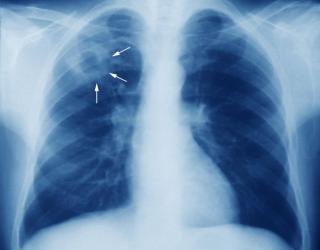

नागपूर : क्षयरुग्णांची नोंदणी न करणाऱ्या रुग्णालयांना शिक्षा